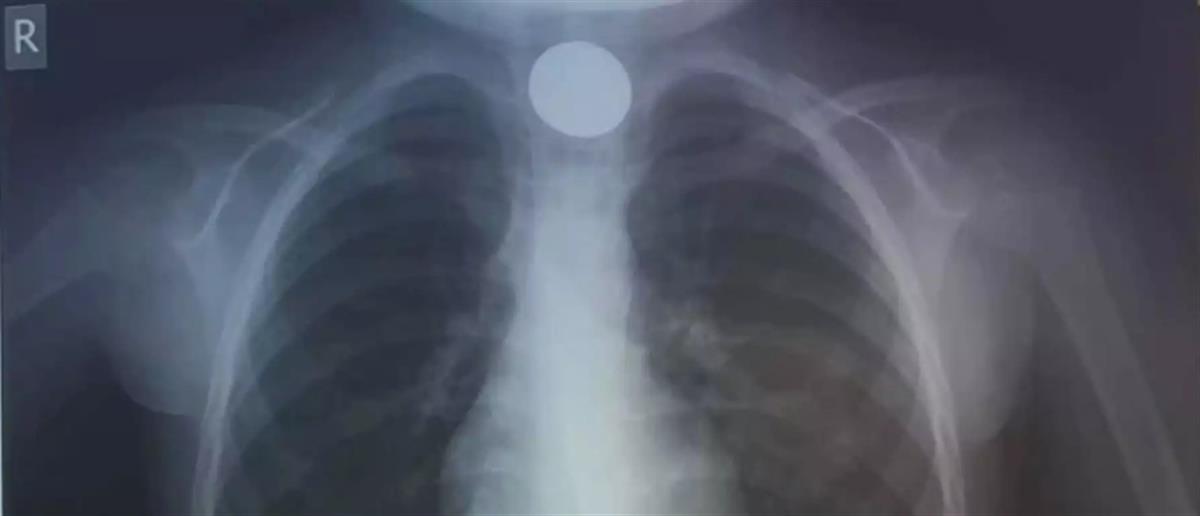

Η πρώτη κίνηση των γιατρών, ήταν να του κάνουν ακτινογραφία, για να δουν το σημείο που είχε σταθεί το νόμισμα.

Οι γιατροί στο ΠΑΓΝΗ κατάφεραν ταχύτατα να αντιμετωπίσουν το περιστατικό και το 4χρονο παιδί επέστρεψε σπίτι του και άλλαξε χρόνο με την οικογένεια του.